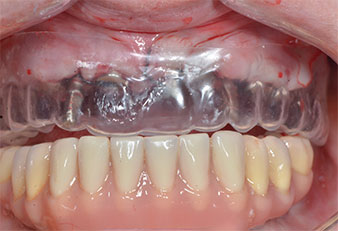

Drei Jahre später war es Zeit für eine gleichartige Oberkieferprothese. Basierend auf der DVT-Planung wurde durch Verwendung kurzer Implantate eine Sinusaugmentation vermieden und die geplanten Implantatpositionen wurden mit einer Bohrschablone auf den Kieferkamm übertragen (Abb. 1 und 2).

Wegen des relativ harten Knochens (D2) an den Positionen 11 und 21 wurden die 10 mm langen Implantatlager in diesem Bereich abschließend mit einem 4-mm-Spiralbohrer, dem chirurgischen Winkelstück WS-75 L von W&H und dem W&H Implantmed Implantologiemotor in Verbindung mit dem optionalen W&H Osstell ISQ module präpariert. Im Gegensatz dazu wurde der weiche Knochen der Implantatlager im Seitenzahnbereich mit dem Piezomed I3P auf den abschließenden Durchmesser von 3 mm erweitert. Die Implantate wurden dann transgingival eingesetzt, die Einheildauer betrug drei Monate (Abb. 6-10). Die vorhandene Prothese wurde auf vier provisorischen Implantaten abgestützt (Abb. 8).